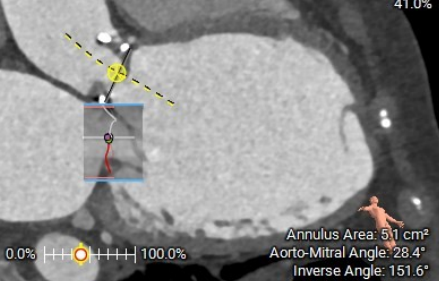

术前CT评估示:

C型环CT测量面积约511.8mm²,直径26.1mm

二尖瓣成形环长径30mm,短径20.5mm

29mm SAPIEN 3瓣膜模拟,无流出道梗阻风险

房间隔穿刺点与二尖瓣关系,距离可

造影C型环几乎无显影,建议食道超声结合造影定位